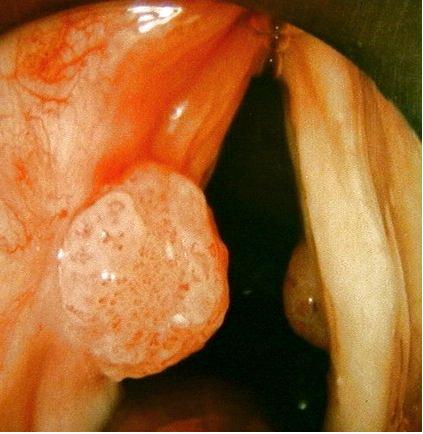

喉癌的早期症状图片

喉癌的早期症状:喉癌最多累及声带,即使体积再小,也会出现声音嘶哑。异物感、紧迫感或吞咽不适感,是声门上型喉癌的早期症状。由于肿瘤刺激可产生刺激性干咳,痰中带血,患者常有粘液粘着感,故常“洗嗓子”。 喉癌合并溃疡、炎症或喉软骨骨膜炎时,可引起神经的反射性疼痛,表现为同侧头痛、耳痛。声带息肉有时也会出现声嘶,其中少数亦可引起癌变。故对声带息肉最好及早手术切除。

喉癌的早期症状图片

喉癌的早期症状:喉癌最多累及声带,即使体积再小,也会出现声音嘶哑。异物感、紧迫感或吞咽不适感,是声门上型喉癌的早期症状。由于肿瘤刺激可产生刺激性干咳,痰中带血,患者常有粘液粘着感,故常“洗嗓子”。 喉癌合并溃疡、炎症或喉软骨骨膜炎时,可引起神经的反射性疼痛,表现为同侧头痛、耳痛。声带息肉有时也会出现声嘶,其中少数亦可引起癌变。故对声带息肉最好及早手术切除。